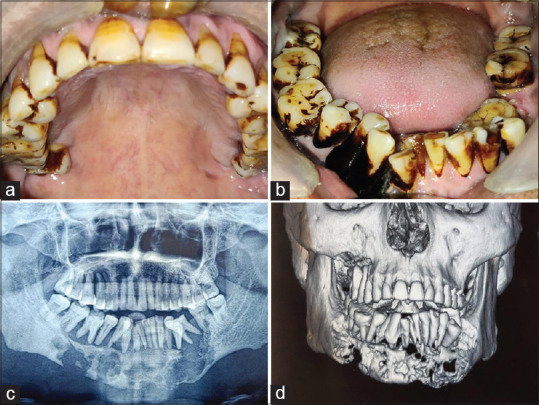

Patient concerns and diagnosis: A 48-year-old male presented with swelling and tooth mobility since 6 months. Orthopantomogram revealed extensive destruction in the mandible and right maxillary posterior region. Histological examination confirmed LCH using immunohistochemical staining with S-100, CD1a.

Outcome: Three months post-treatment, remission was observed, though some residual lesion remained. Follow-up at six months showed no further disease progression, supporting the efficacy of corticosteroid injections.